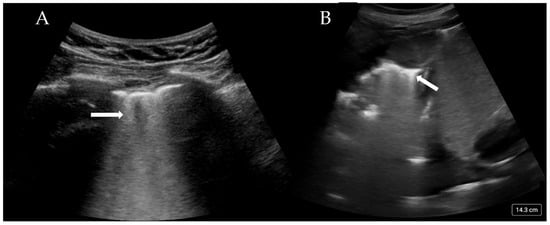

| Pneumothorax | Absent lung sliding Stratosphere sign/barcode sign M-mode demonstrates only parallel horizontal lines indicating no aerated lung Lung pulse—absence of lung sliding with pulsed motion synchronous to heartbeat Lung Point—point at which pneumothorax meets with normal lung sliding |

| Pleural effusion | Interpleural hypo/anechoic space (Figure 3A,B) Jelly fish sign—lung moving within effusion appears jelly fish like |